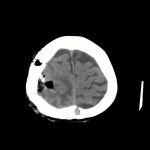

髄膜腫

(右穹隆部)

断層撮影

No.’15_144 手術前1

No.’15_144 手術後